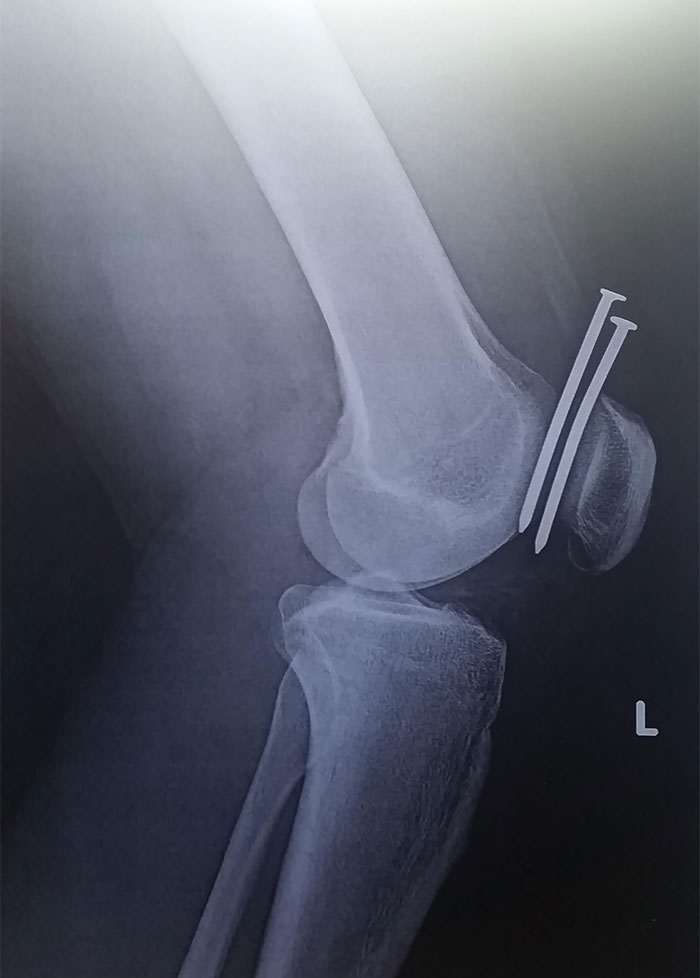

Не шутите с гвоздезабивным пистолетом

Бестолковое лечение иглоукалыванием при артрозе левого колена